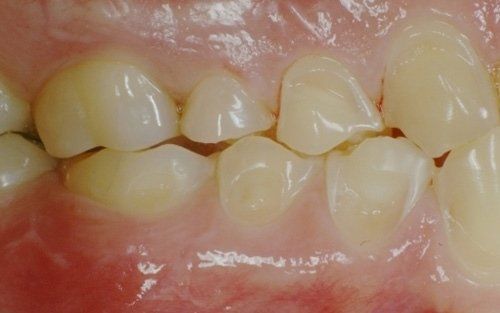

Erosion is the phenomenon whereby dental enamel undergoes a gradual dissolution due to the constant presence, in the oral cavity, of acidic substances mainly from certain types of beverages (cola, iced tea, sports supplements, etc.) or from the stomach (gastroesophageal reflux, vomiting induced in bulimic/anorexic patients).

The constant presence of acidic substances causes the gradual loss of the hard tissues of the tooth

and the consequent modification of both the aesthetics of the tooth and its dimensions. The patient often begins to stop smiling, ashamed of the appearance their teeth have taken, in addition to frequently experiencing dental sensitivity that develops proportionally to the progression of the process. Sometimes this phenomenon is associated with